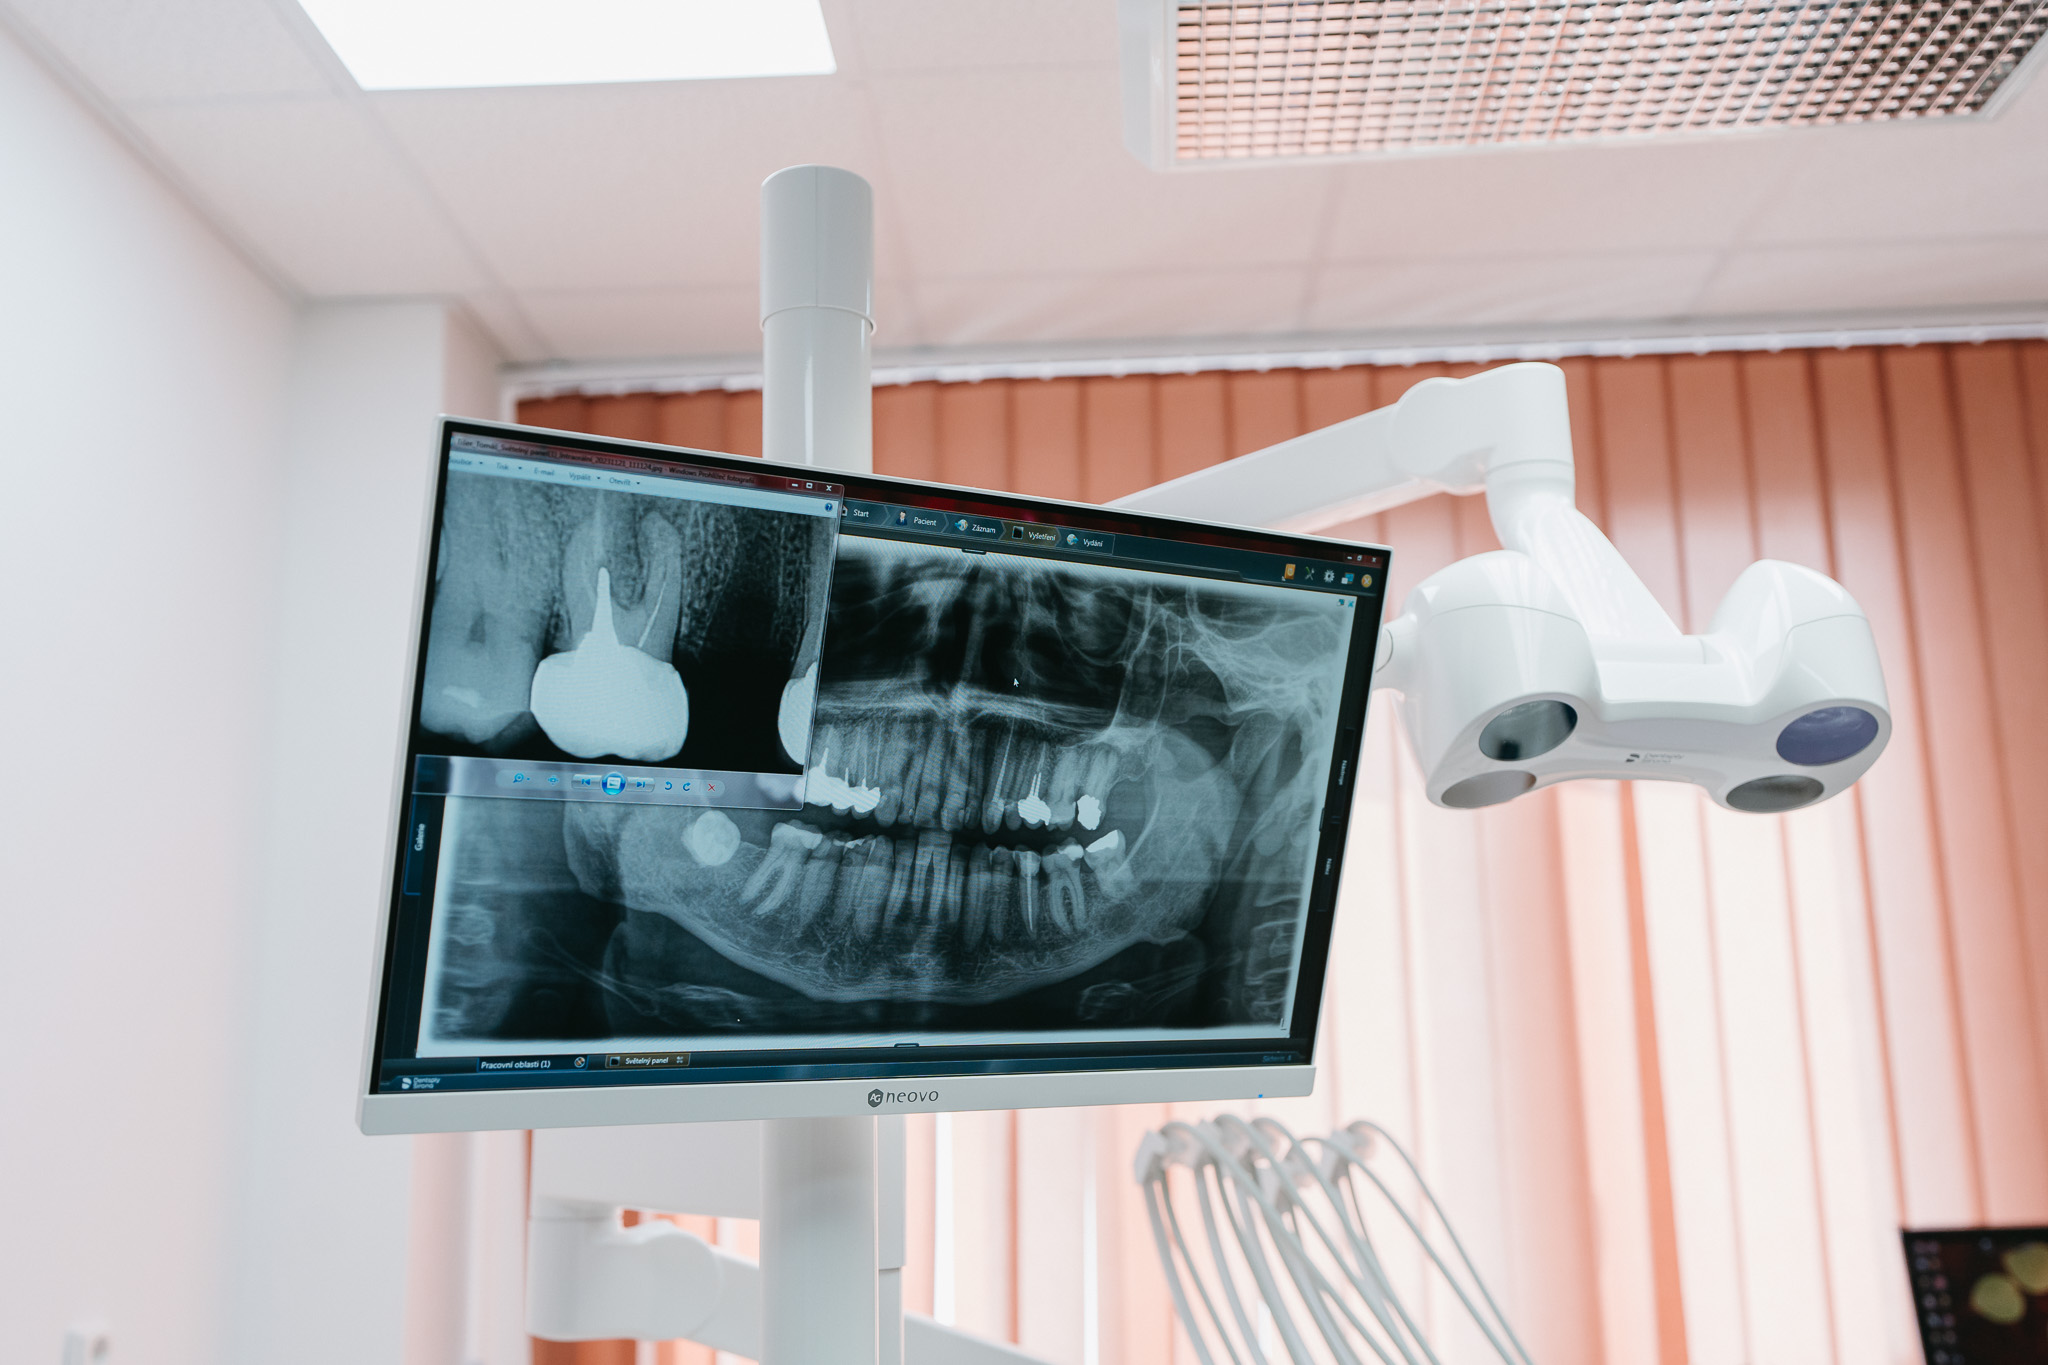

OPG-RTG

Rentgenový snímek je nedílnou součástí stomatologického vyšetření a ošetření, protože nám umožňuje nahlédnout do struktur tkání, které pouhým okem nejsou viditelné. Pomocí rentgenového zobrazení dokážeme odhalit možné deformity a patologie tvrdých tkání, nedostatečně ošetřené kořenové kanálky, cysty a další problémy.

Na naší klinice máme k dispozici moderní rentgenové přístroje přímo na místě, což umožňuje rychlé a přesné diagnostické zobrazení bez nutnosti návštěvy jiného pracoviště. Zhotovujeme ortopanoramatické snímky (OPG), intraorální snímky a v případě potřeby nabízíme i 3D snímkování, které se využívá například při navigované implantaci pro přesnější a bezpečnější umístění implantátů.